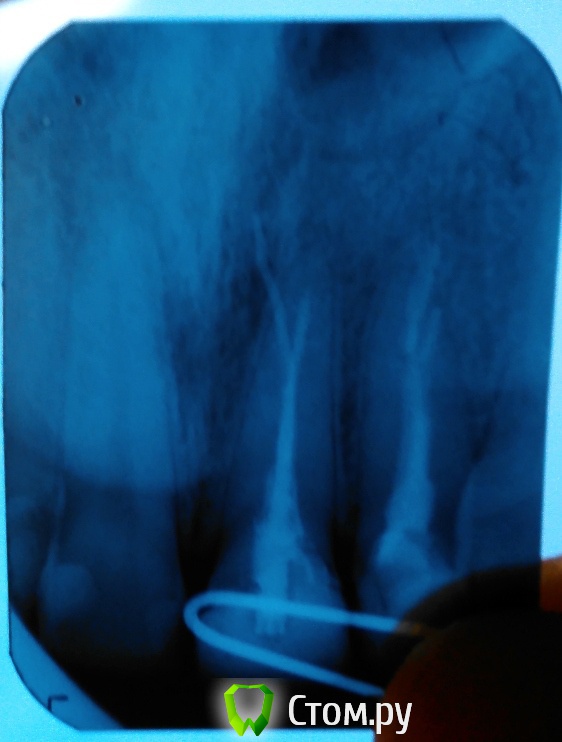

Romannk Опубликовано 16 августа, 2014 Поделиться Опубликовано 16 августа, 2014 (изменено) эти два зуба являются проблемными (1,2) перелеченными 2-3 раза.в 2008 я сделал резекцию по удалению остаточного пломб материала, в 2009 мне их перелечили, перекладывали лекарство, вставили гуттаперчивые штифты.зубы потемнели мне сняли потемневшую эмаль, покрыли световой пломбой, но зуб не выдержал и отвалилась коронковая часть, вставили штифт титановый, наростили зуб.сейчас мне предлагают сделать повт. резекцию, т.к. пломб материал вышел опять за пределы. в эндонтическом лечении говорят смысла нет. типо что там все нормально, но мне кажется что там есть воспаление.посмотрите пожалуйста, т.к. мне кажется без эндодонтического лечения боль останется. Изменено 16 августа, 2014 пользователем Romannk Ссылка на комментарий

Гарриевич Опубликовано 17 августа, 2014 Поделиться Опубликовано 17 августа, 2014 Плохое качество снимка, видно только что пломбировочный материал за пределами корня Ссылка на комментарий

faity Опубликовано 18 августа, 2014 Поделиться Опубликовано 18 августа, 2014 а другим врачам сложно ответить?не сложно, просто не все часто читают обновления снимок переделать, воспаление скорее всего есть, если найдете эндодонта со скопом- может вытащить штифт из-за канала Ссылка на комментарий